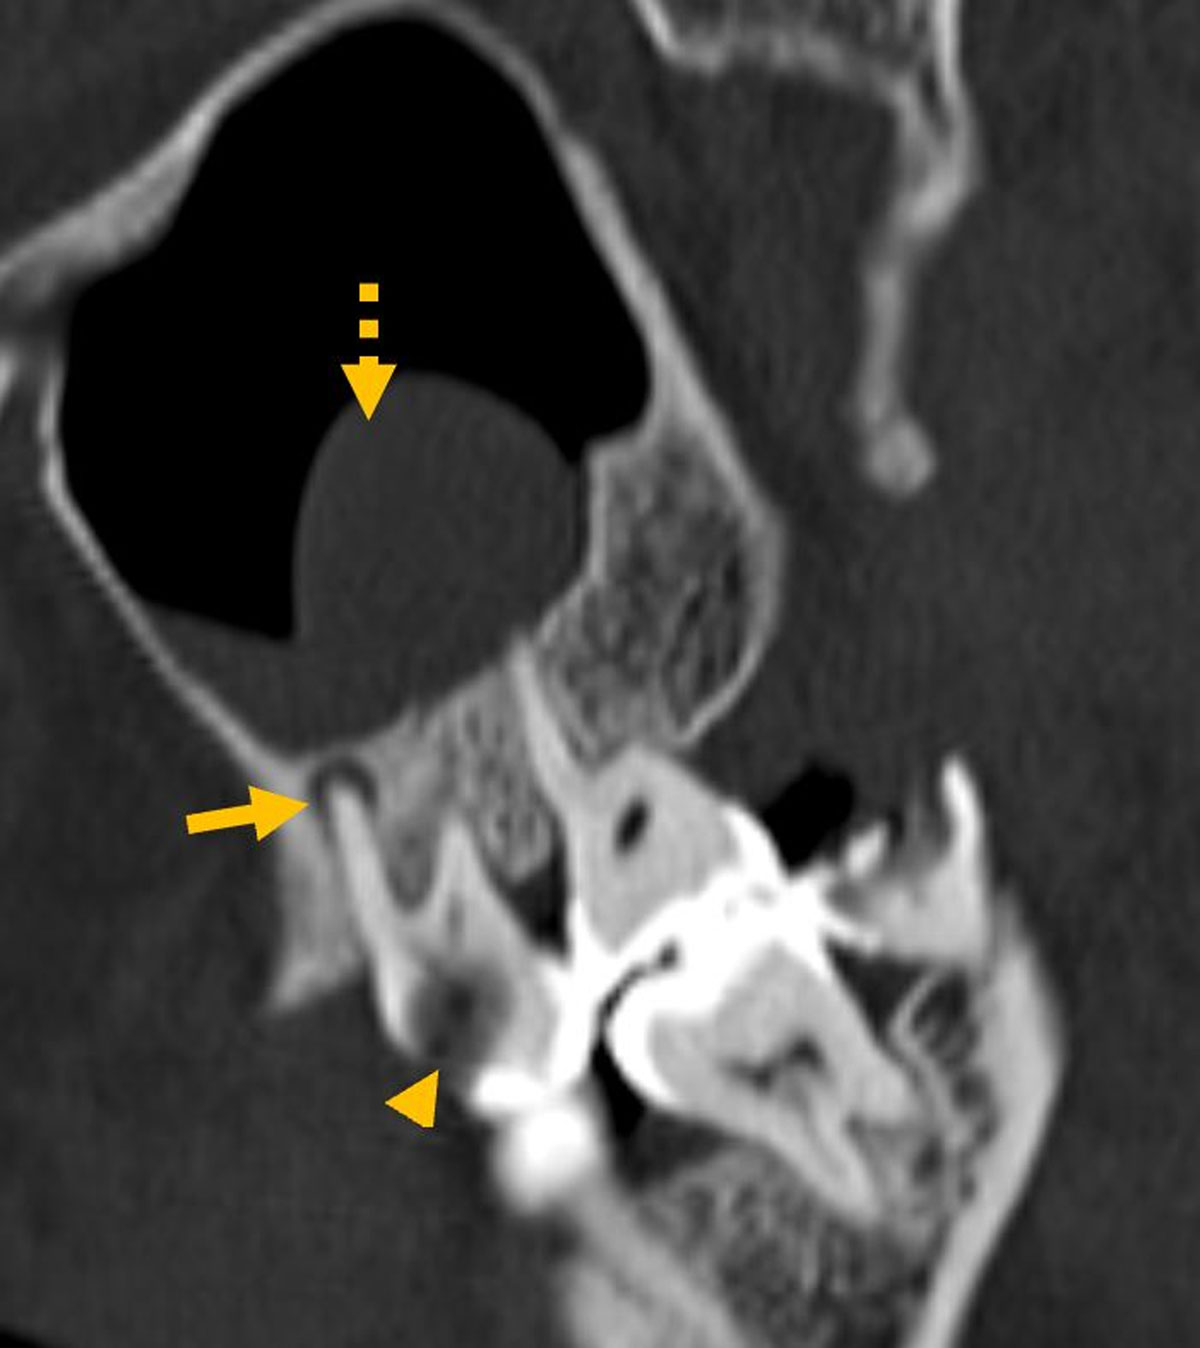

Figure 1

Dental caries (arrowhead) and periapical lucency (arrow) in the same tooth with adjacent polypoidal mucosal thickening (dashed arrow).